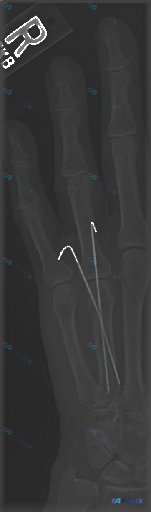

整理一份右手指部的X光正位影像资料,最醒目的是两枚金属克氏针——一枚从第3掌骨基底部穿到近节指骨,另一枚对应第4指,两根都跨了掌指关节,近端还在皮下留了钩状弯曲。 骨皮质能看到不连续或者陈旧性骨折线的痕迹,目前没看到明显的溶骨、广泛骨膜反应,植入物周围也没有透亮带。 问题来了:如果问“这张影像里有什...